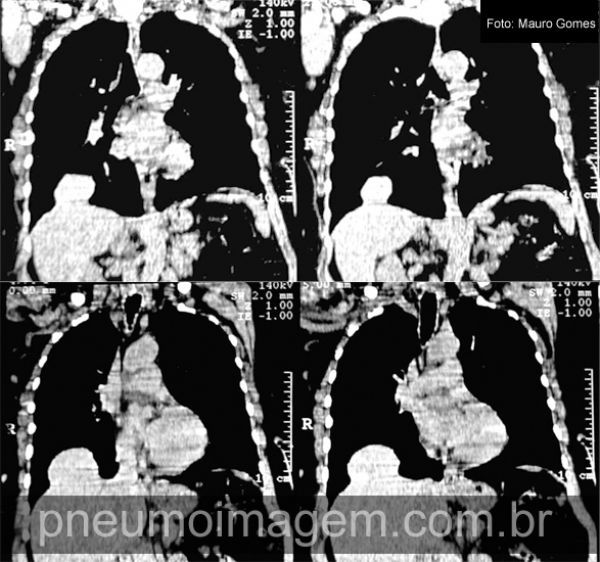

Cortes tomográficos demonstrando o fígado invaginando-se para dentro da cavidade torácica, mas sem lesão do diafragma. Na eventração diafragmática o diafragma mantém sua continuidade e a inserção na margem costal.

CT slices showing the liver into the chest cavity, but without diaphragm injury. In eventration diaphragmatic diaphragm maintains its continuity and the inclusion in the costal margin.